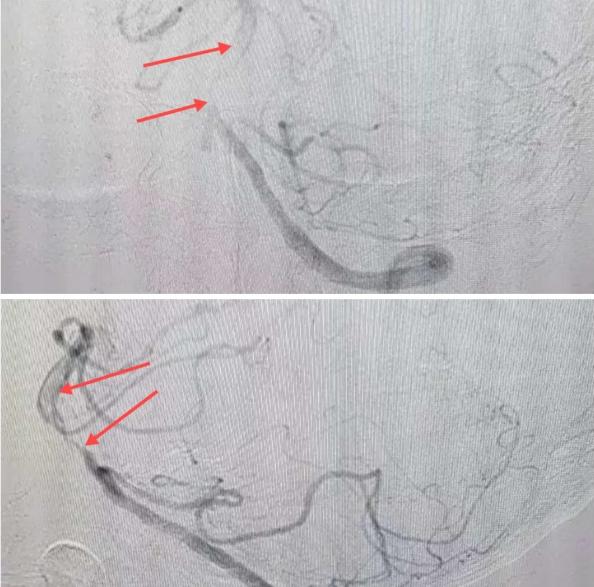

在經(jīng)造影后,主刀醫(yī)生腦一科副主任楊慶堂發(fā)現(xiàn)患者基底動(dòng)脈下段重度狹窄且狹窄段以遠(yuǎn)有大負(fù)荷血栓,其狹窄處考慮為動(dòng)脈夾層,手術(shù)難度及風(fēng)險(xiǎn)較大。楊慶堂副主任在彭壯副主任醫(yī)師的協(xié)助下運(yùn)用spaceman(太空人)技術(shù),中間導(dǎo)管抵近血栓抽吸配合支架拉栓,成功開(kāi)通血管。再次造影可見(jiàn)基底動(dòng)脈管腔明顯增寬,遠(yuǎn)端血管顯影良好,且等待20分鐘后造影仍顯示血流通暢。楊慶堂副主任考慮到本次手術(shù)時(shí)間不宜過(guò)長(zhǎng),現(xiàn)患者基底動(dòng)脈及分支前向血流維持良好,給予其抗栓藥物應(yīng)用后結(jié)束手術(shù),并建議患者3個(gè)月后復(fù)查造影,明確其基底動(dòng)脈夾層情況。

造影可見(jiàn)血管夾層和大量血栓形成